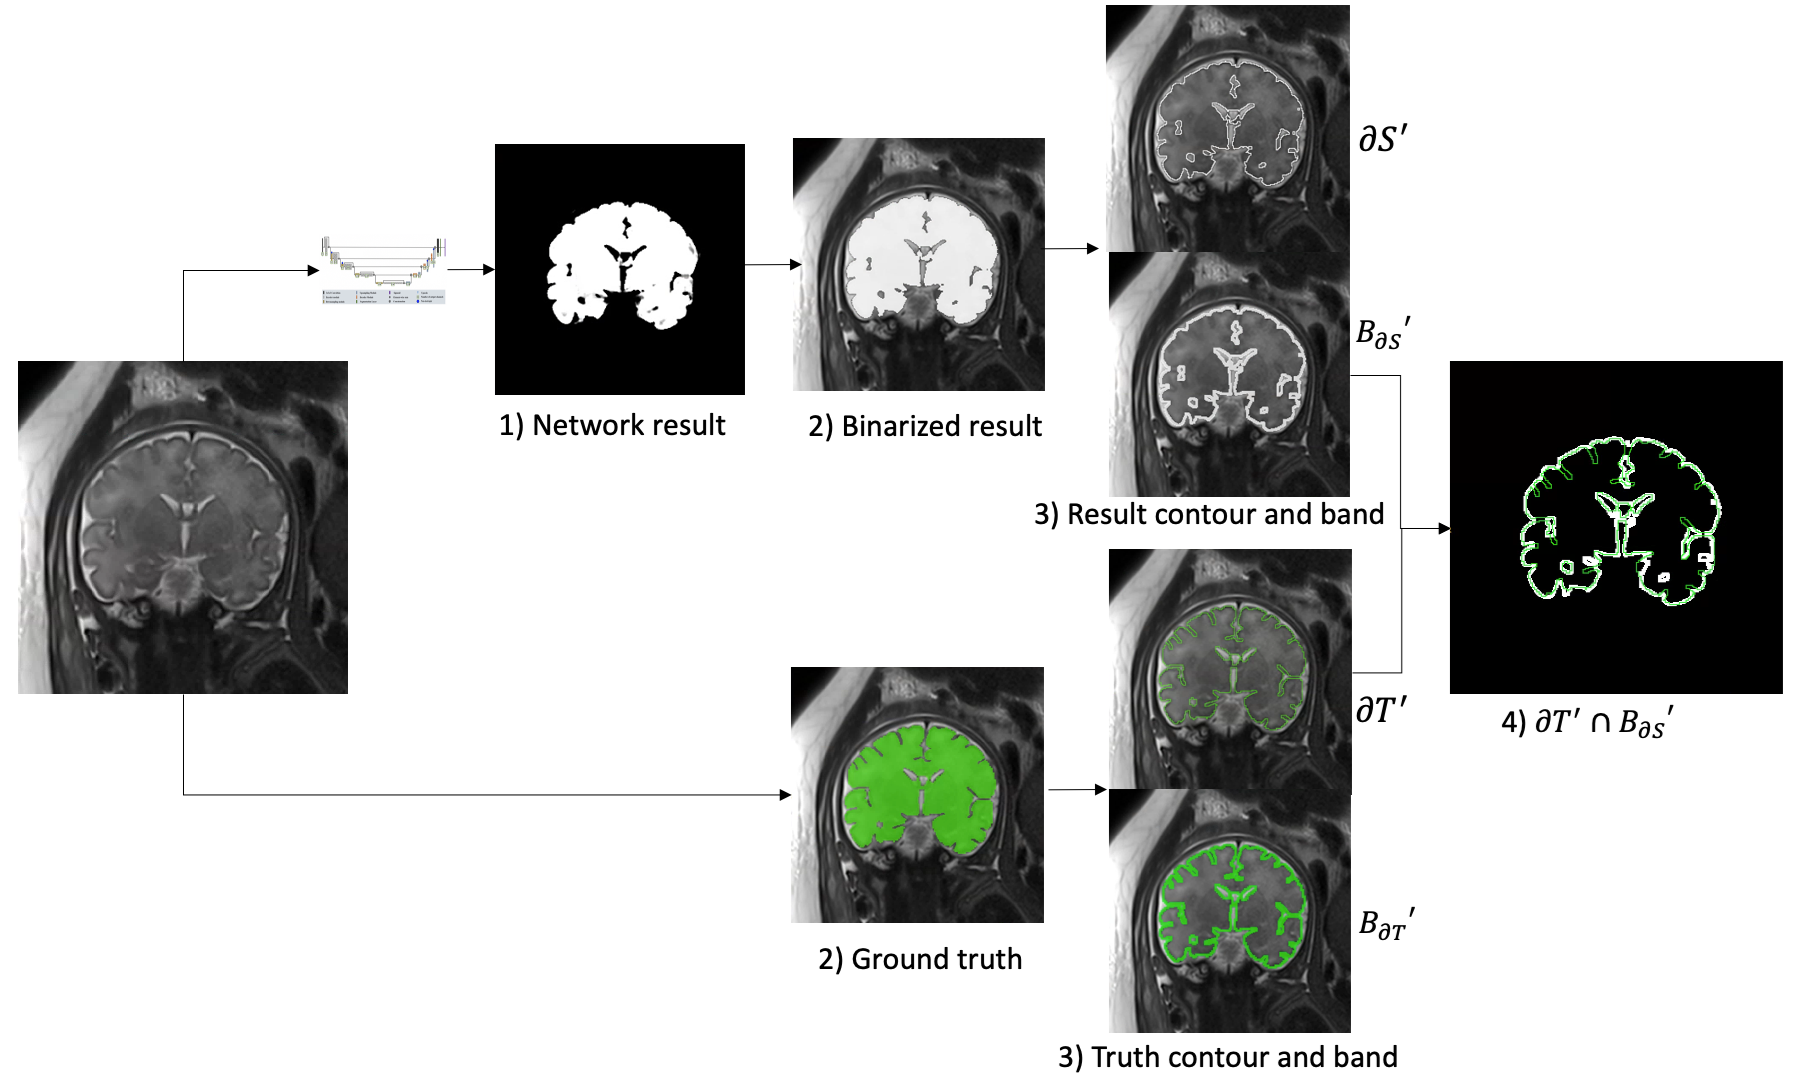

For the Contour Dice loss function calculation, we estimate the segmentation contours and from Eq. 1 with the erosion and XOR operators (Fig. 1). As a result, the computed contours have a width. We can now integrate over the contour voxels and formulate a loss function that is very similar to the original Contour Dice metric in Eq. 1.

The contour Dice loss calculation is performed in two steps: 1) Contour and band extraction for ground truth segmentation and binarized segmentation result; 2) Dice with Contour dice loss computation. Fig. 2 illustrates the Contour Dice computation using the extracted contours and bands.

3.1 Contours and Bands Extraction

The segmentation contour and the band around it are computed as follows. First, binary thresholding is applied to the network output with a predefined threshold . Then, the contours of both the network result and the ground truth segmentation are extracted using erosion and XOR operations (Fig. 1). Finally, the bands are extracted using erosion, dilation and XOR operations (Fig. 3).